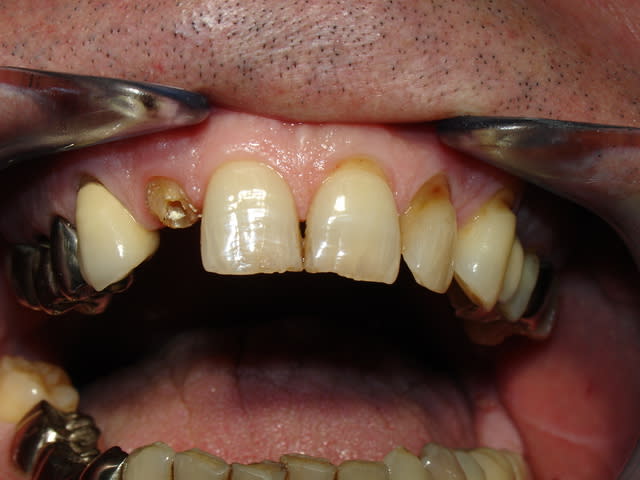

Quelques images de l'année dernière

Vue vest gfv3yx - Eugenol